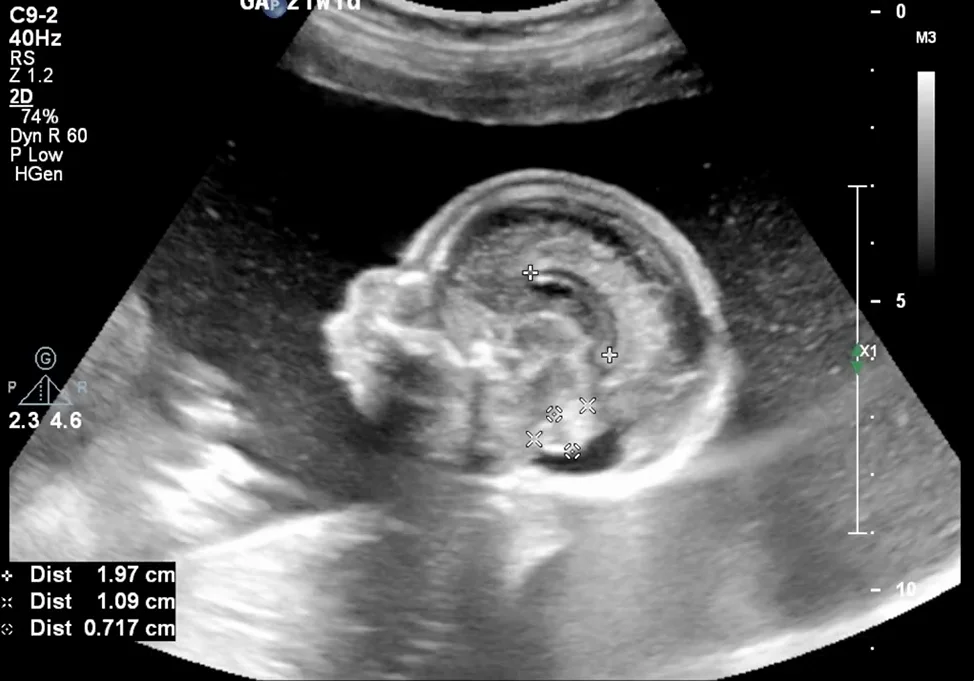

Hội chứng Treacher Collins (Treacher Collins Syndrome) - đầu mặt